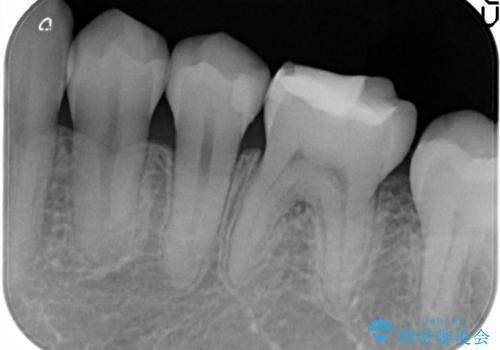

- 定期検診において虫歯を見つけた患者様です。

セラミックインレーにて修復治療をしています。

当院のセラミックインレーはすべてプレスという製法で製作しております。削り出しのものより精度が高く製作可能です。